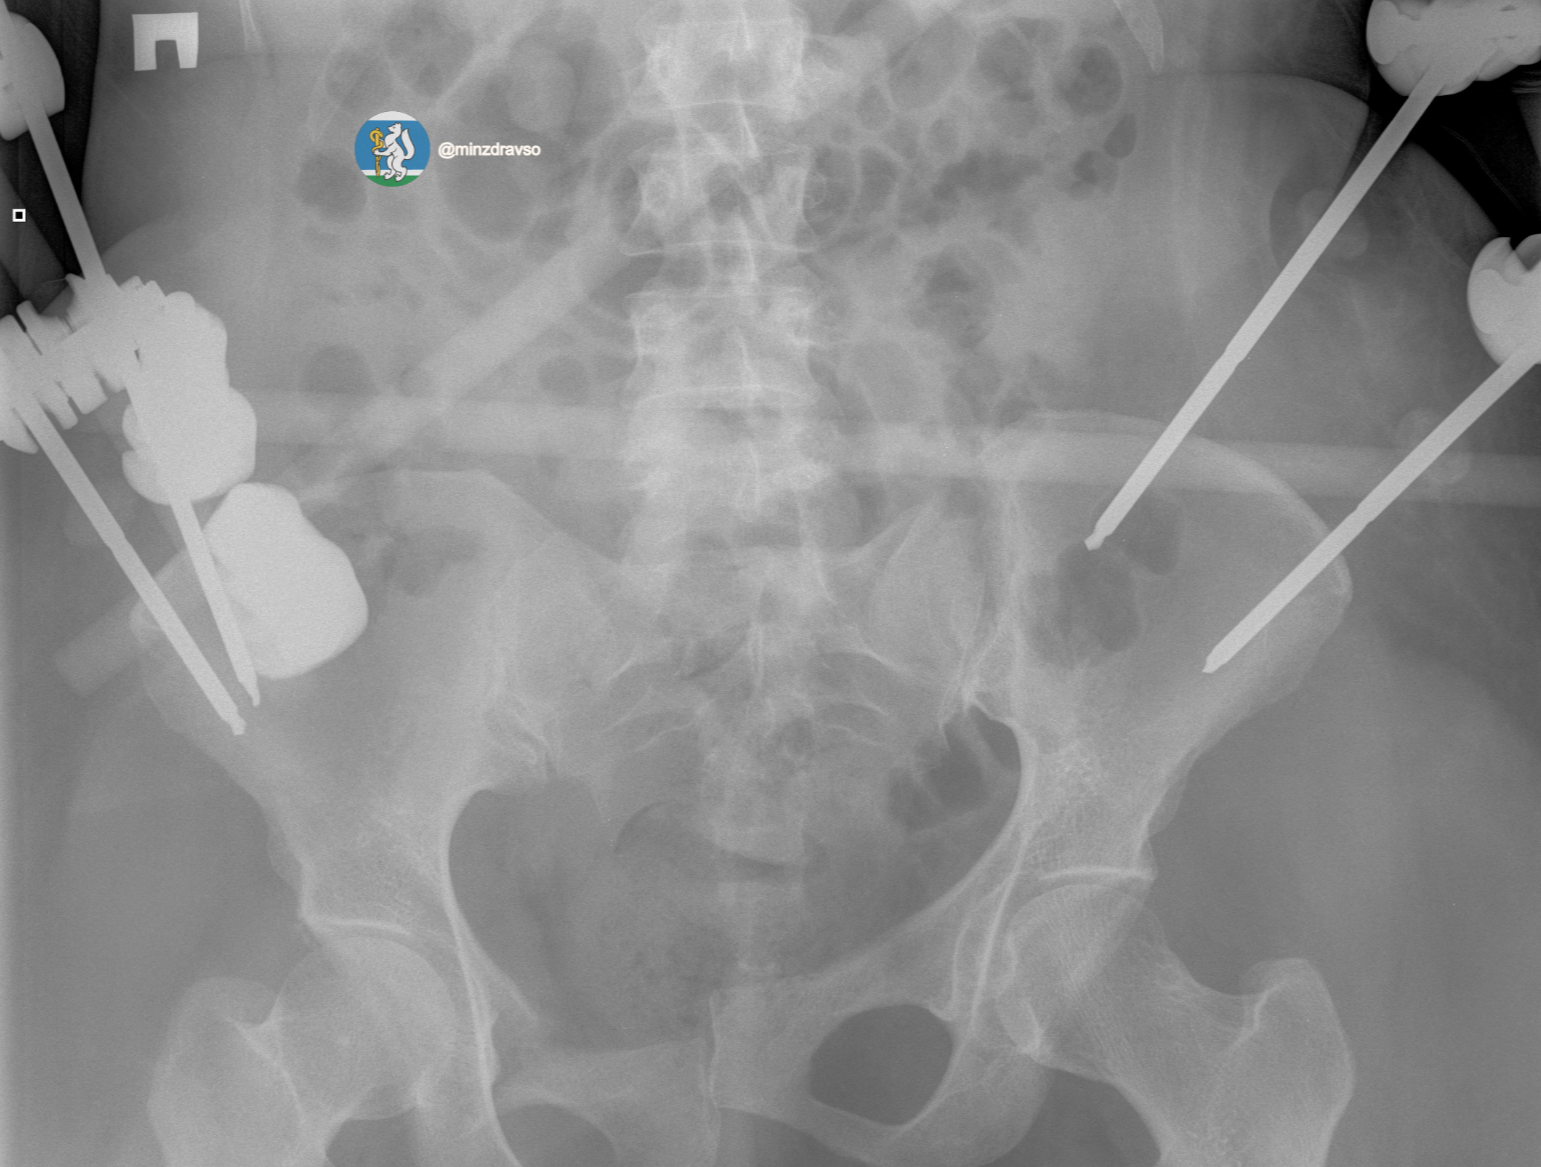

В течение первых 15 минут были проведены все необходимые исследования. Врачи диагностировали тяжелую политравму, включающую закрытую черепно-мозговую травму, ушиб головного мозга, повреждение челюстно-лицевых костей, ребер, двусторонний пневмоторакс, оскольчатый перелом правой ключицы и раздробленные кости таза. Крайне тяжелое повреждение таза представляло высокий риск массивной кровопотери, поэтому борьба за жизнь пациентки началась с немедленной стабилизации ее состояния.

«Пострадавшей оказали помощь, которая отвечает всем современным требованиям к лечению политравмы. Чтобы стабилизировать зоны переломов и купировать болевой синдром, врачи скрепили отломки костей всех поврежденных сегментов костей и таза аппаратами внешней фиксации. Большую роль сыграл мультидисциплинарный подход: спасти пациентку удалось благодаря совместной работе анестезиологов-реаниматологов, травматологов-хирургов и нейрохирургов», – рассказал заведующий травматологическим отделением Городской больницы №36 «Травматологическая», к.м.н. Евгений Козлов.

Профессионализм и опыт врачей, их высочайшая квалификация и плановое совершенствование экстренной медицинской помощи в Свердловской области позволили пациентке получить второй день рождения. Тактика врачей позволила купировать шоковое состояние и подготовить организм к основному хирургическому этапу. Череду вмешательств завершил демонтаж аппаратов внешней фиксации таза и установка внутренних металлофиксаторов на ключицу и кости таза.